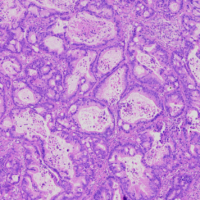

SINGLE-CELL RNA SEQUENCING ON FORMALIN-FIXED AND PARAFFIN-EMBEDDED (FFPE) TISSUE IDENTIFIED MULTI-CILIARY CELLS IN BREAST CANCER

Proyecto de investigación donde se han utilizado muestras y datos de pacientes que han donado a Biobanco. El objetivo de este estudio fue evaluar la idoneidad de los tejidos fijados en formol y posteriormente incluidos en parafina y muestras en fresco frescas fijadas para la secuenciación de ARN de una sola célula, en tumores de…